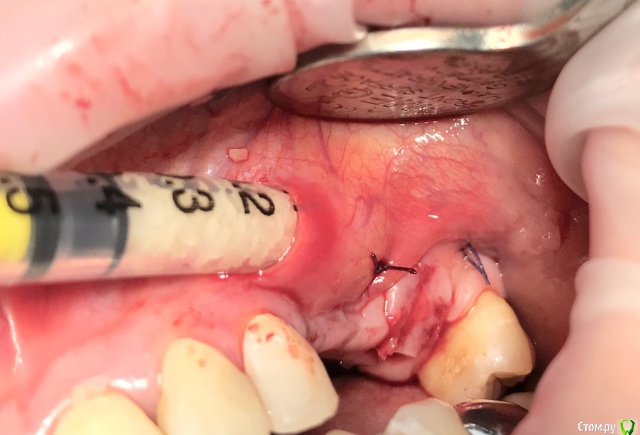

колесников Опубликовано 20 августа, 2019 Автор Поделиться Опубликовано 20 августа, 2019 Очередной случай тоннельной пластики альвеолярного гребня. Был небольшой бонус в виде лунки 26го зуба с дефектом вестибулярной стенки и оас. Лунка консервирована и закрыта «быстрым Ноймайером»,24,25 тоннельный графтинг. Графт тот же,шурос кортикальный без добавок.Контроль и имплантация через 4 мес,через неделю фиксация временной реставрации. Через 2-3 проверим на состоятельность. 4 Ссылка на комментарий